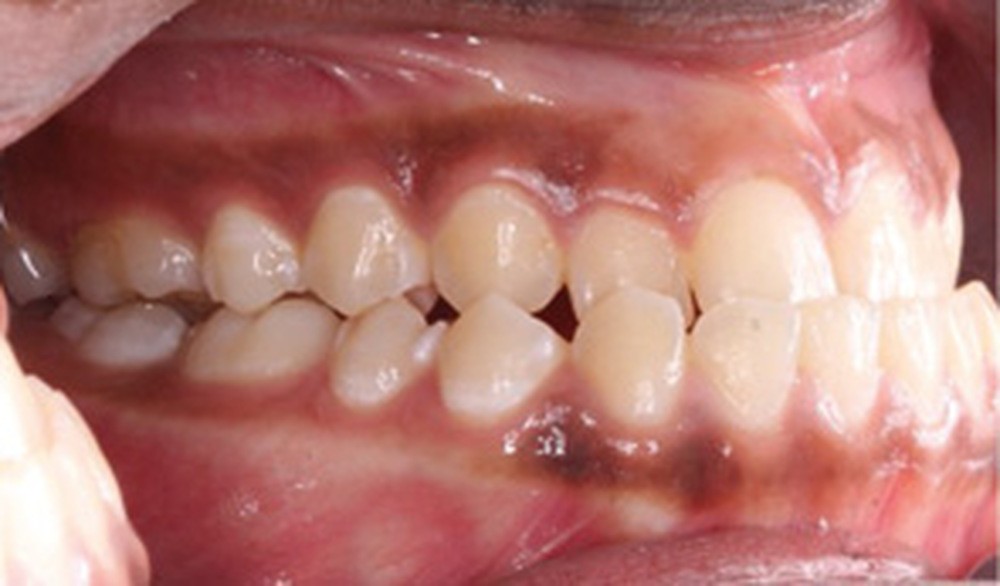

Examen clinique (fig. 1a-h)

À l’examen de face, Anisa présente un visage ovalaire, des hémifaces symétriques, des lignes horizontales parallèles, une augmentation de l’étage inférieur, une occlusion labiale légèrement forcée et des dents mandibulaires exposées au sourire. Les profils général et sous-nasal sont concaves avec un angle naso-labial augmenté et une prochéilie inférieure.

L’examen clinique endo-buccal révèle une denture adulte jeune avec un inversé d’articulé antérieur de 13 à 23, des tatouages gingivaux ethniques et des taches de décalcifications, un parodonte sain mais un brossage insuffisant.

L’arcade maxillaire est en V et la voûte palatine profonde. L’arcade mandibulaire a une forme en U (non-concordance des formes d’arcade) et présente des malpositions des dents cuspidées. La médiane mandibulaire est décalée à gauche de 2 mm ; le recouvrement antérieur est de 2 mm ; les molaires sont en classe III avec un surplomb inversé.